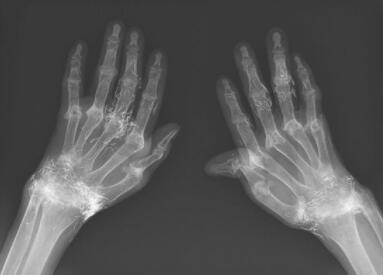

程本维专家指出类风湿的诊断可不是光看类风湿因子就

在类风湿性关节炎的诊断中都会用到哪些比较实际的方法呢或许需求经过哪些鉴定项目呢。程本…[详情]

河南风湿病医院怎么样? 类风湿关节炎是一种病因未明的慢性、以炎性滑膜炎为主的风湿免疫…[详情]

郑州类风湿专科医院简述得了类风湿后要如何饮食?类风湿关节炎是一种病因未明的慢性、以炎…[详情]

LFS16020077 姓名:李女士 性别:女 年龄:52岁

- 病情

RA ①晚期 ②并发症 病史:8年+

- 治疗

疗后患者双膝下蹲自由,上下台阶无压力,双腕关节、双手掌指关节疼痛消失,双手指恢复关节功能,整个人面色恢复,身体各项机能均提升。